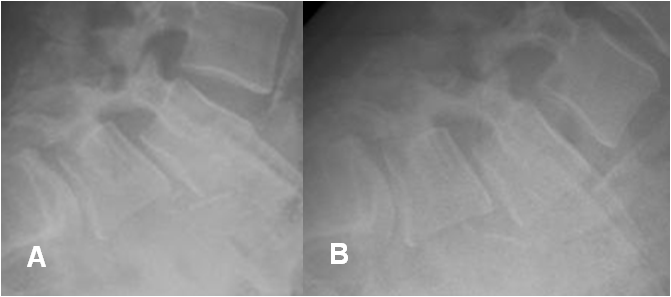

Fig 75. Inestabilidad.

A: Rx lateral neutra y B: Rx lateral en flexión. Anterolistesis GI-II de L4 sobre L5 y GI de L5, sobre S1, que no se modifica con la flexión.